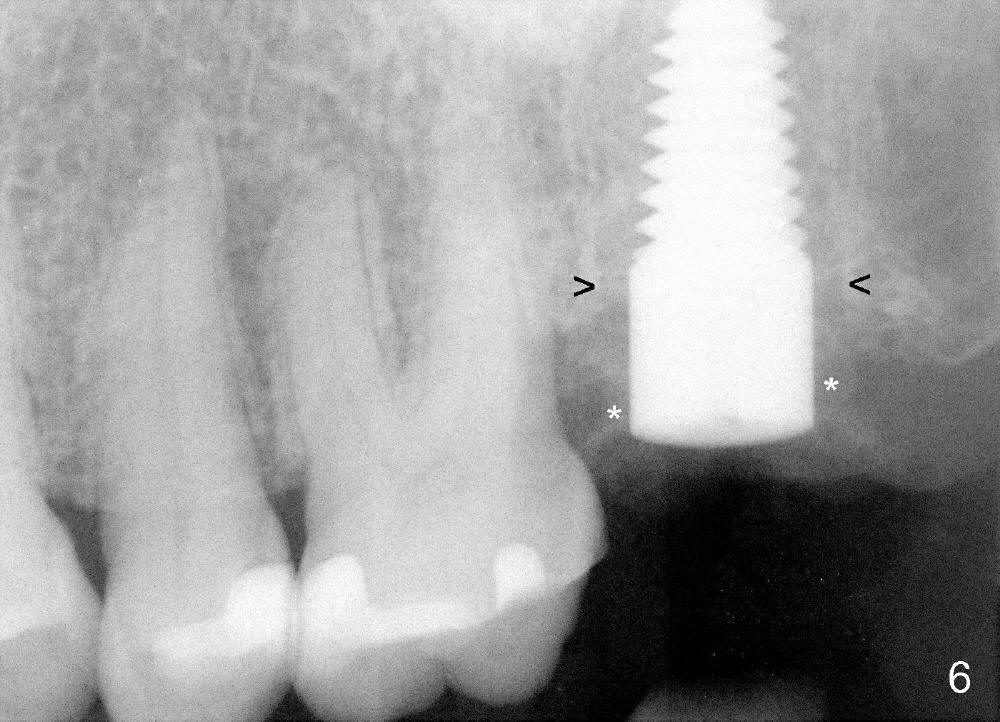

A 57-year-old lady presents for abscess buccal to the tooth #15 (Fig.1 A). Mesial and distal to the occlusal composite (Fig.2 C) is a crack line. In addition to long furcated roots, the upper border of the bone is not shown in this preop PA (arrow). Fig.3 is taken to show a thin septum surrounded by the mesiobuccal (MB), distobuccal (DB) and palatal (P) sockets (Fig.3). Osteotomy is initiated in the septum by 1.2 and 1.5 mm pilot drills, followed by 2,3,4 mm rounded tapered osteotomy at the depth of 17 mm. Nose blowing test is carried out after each step with negative result. Stability is achieved when a 4.5 mm tap is inserted at 17 mm, but the upper end of the tap is not visible (Fig.4,5). When a 5 mm tap is placed, stability is decreased, probably because the coronal end of the septum starts to break down (due to expansion). To re-gain stability, the 5 mm tap needs to go deeper. A 6 mm tap also achieves satisfactory stability at 20 mm. When the tap is removed, there is no air leakage. A 6x20 mm implant is placed with insertion torque > 60 Ncm; the upper end of the implant is still out of view in PA (Fig.6). Another problem is that the implant needs to go deeper to obtain sufficient occlusal clearance. The lower first molars and the 2nd premolars are missing. A panoramic X-ray has to be taken to show the apical end of the implant: ~ 3 mm into the sinus (Fig.7 ^). The maxillary tuberosity appears to grow downward (arrow). In other word, the tooth #15 appears to have been intruded due to overloading.